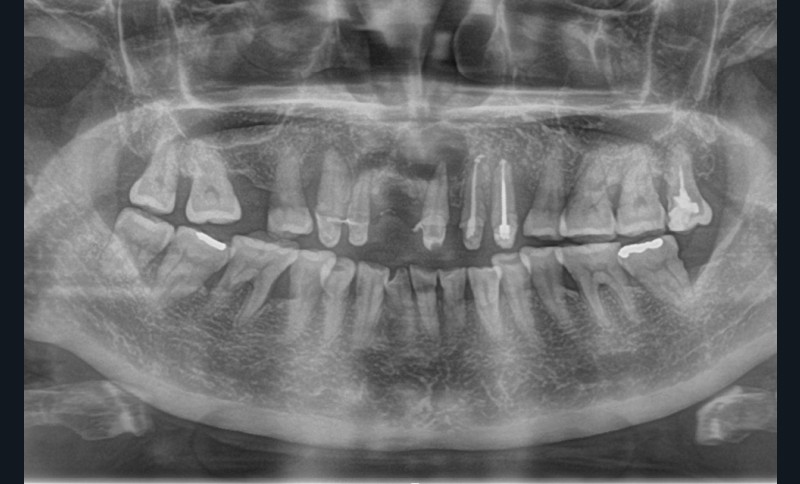

Le kyste radiculo-dentaire (fig. 1 et 2), également retrouvé sous le terme de kyste apico-dentaire, ou radiculaire, est le plus fréquent des kystes des maxillaires [1]. Il s’intègre dans la grande famille des tumeurs bénignes osseuses odontogéniques et maxillo-faciales (classification internationale de l’OMS, 2017). Il se développe aux dépens d’un granulome péri-apical secondaire à une nécrose dentaire. Le mécanisme physiopathologique à l’origine de la formation kystique est la prolifération de débris épithéliaux (débris de Malassez) présents dans le desmodonte sous l’action de stimuli inflammatoires. Un kyste est constitué d’une membrane épithéliale et d’une cavité plus ou moins liquidienne, voire solide dans certains cas. On y retrouve des cristaux de cholestérol, des calcifications dystrophiques d’exsudat inflammatoire, des macrophages, des plasmocytes, des cellules ciliées, muqueuses, géantes multinuclées et, dans certains cas, des globules rouges.

On distingue classiquement le granulome (- 1 cm) du kyste (+ 1 cm). Ce dernier possède des parois propres et des contours réguliers bien délimités. Le développement kystique s’accompagne volontiers d’un refoulement des structures avoisinantes, les corticales osseuses apparaissent soufflées, dans certains cas, amincies, pouvant venir empiéter sur des éléments anatomiques de la sphère maxillo-mandibulaire (sinus, canal mandibulaire, fosses nasales, foramen mentonnier…) (fig. 3).